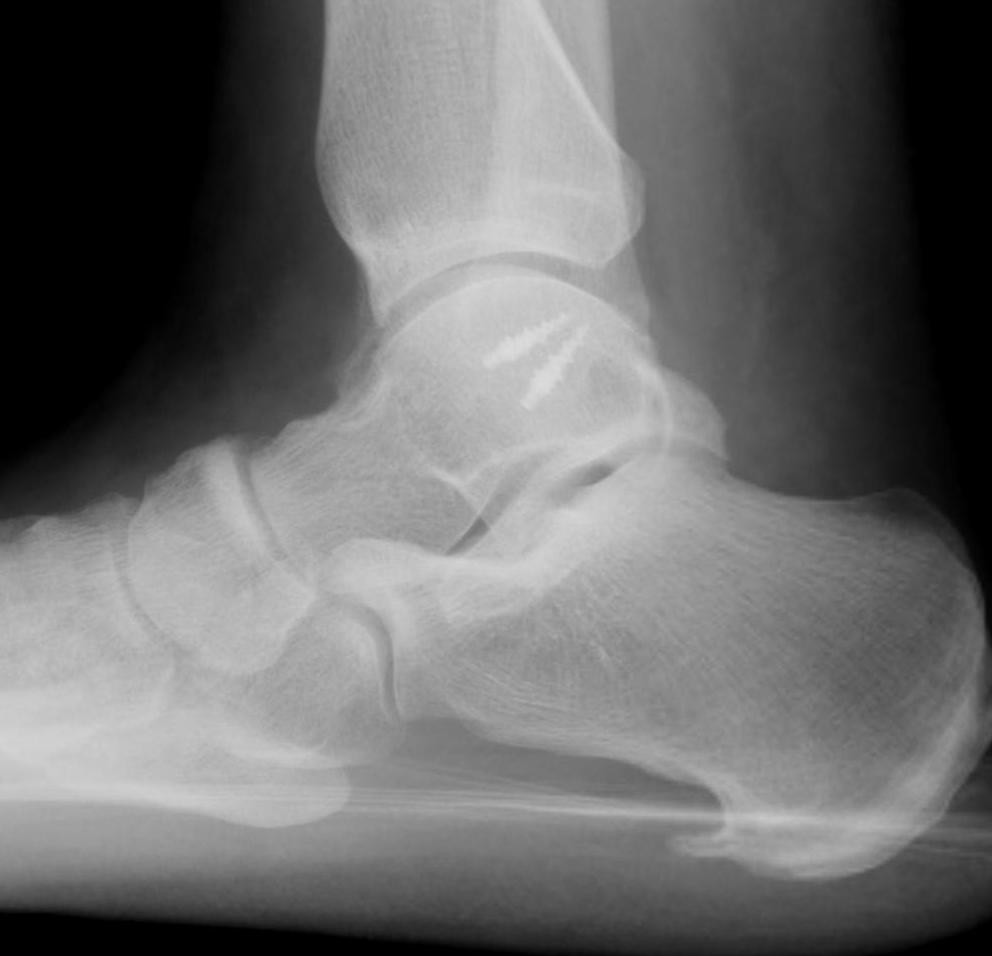

Xrays

Osteochondral lesions

Loose bodies

Stress Xrays

![]() |

ATFL tear

CFL tear